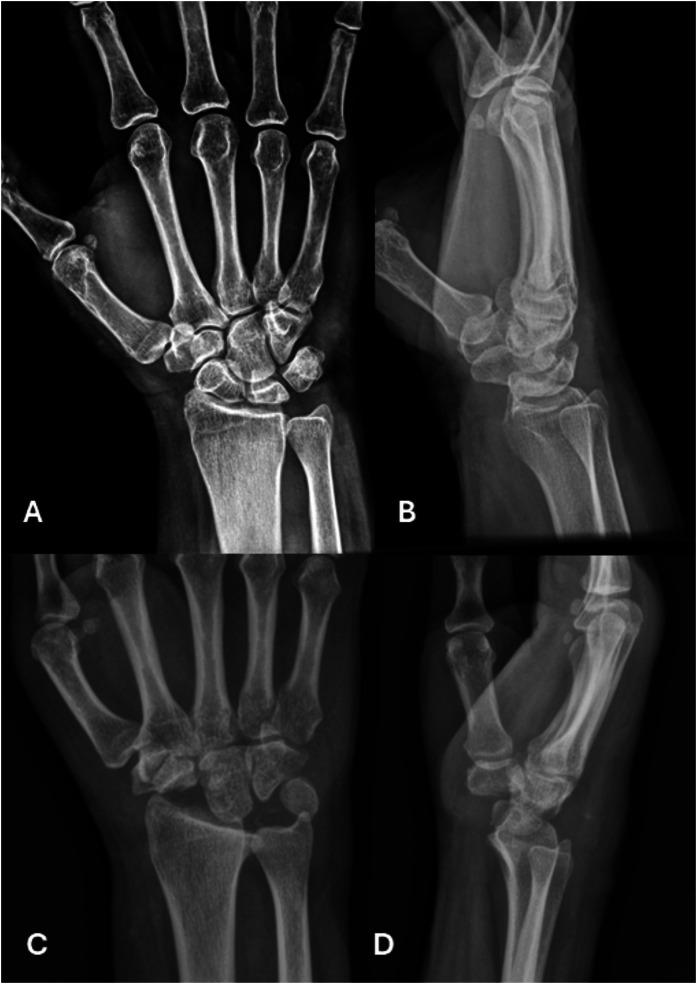

肯博克病:认识与治疗的最新进展

Kienböck Disease: Recent Advances in Understanding and Management.

➢ An at-risk lunate (due to anatomic factors) subjected to a trigger event (axial load, embolism, hypercoagulability) leads to the development of lunate osteonecrosis.➢ Children, adolescents, and elderly patients with Kienböck disease respond well to nonoperative treatments, and this should be considered before any surgical intervention.➢ For disease limited to the lunate, treatment decisions should be driven by the condition of the cartilage; intact lunate cartilage can be treated with joint leveling or core decompression, whereas disrupted cartilage surfaces should be bypassed with scaphocapitate or scaphotrapeziotrapezoid arthrodesis. Newer surgical procedures such as wrist arthroscopy and the introduction of contrast-enhanced magnetic resonance imaging have expanded the treatment options for these patients.➢ Once disease extends outside of the lunate, reconstruction with proximal row carpectomy or partial or total wrist arthrodesis should be considered on the basis of which articular surfaces are affected.➢ The new unified classification system and treatment are applicable to almost all patients with Kienböck disease.

摘要

➢ (由于解剖因素)处于风险中的月骨受到触发事件(轴向负荷、栓塞、高凝状态)影响会导致月骨缺血性坏死的发生。

➢ 患有月骨无菌性坏死的儿童、青少年和老年患者对非手术治疗反应良好,在进行任何手术干预之前都应考虑这一点。

➢ 对于局限于月骨的疾病,治疗决策应取决于软骨的状况;月骨软骨完整时可采用关节平整或髓芯减压治疗,而软骨表面受损时应采用舟头或舟大多角小多角关节融合术绕过。腕关节镜检查和引入对比增强磁共振成像等新的手术方法扩大了这些患者的治疗选择。

➢ 一旦疾病扩展至月骨以外,应根据受影响的关节面考虑采用近排腕骨切除术或部分或全腕关节融合术进行重建。

➢ 新的统一分类系统和治疗方法适用于几乎所有月骨无菌性坏死患者。